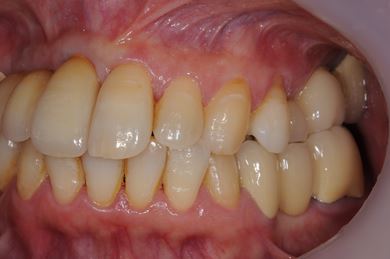

抜歯即日スピードインプラント治療+セラミック治療

| 性別/年齢 | 女性 / 49歳 | ||||||||||||||||||||||||||||||||

| 主訴 | 左奥歯のつめものが取れている所を治療したい。 | ||||||||||||||||||||||||||||||||

| 治療方針 | 抜歯と同時にインプラント埋入を行い、治療期間を短縮する。上前歯部、骨再生法によりインプラント治療を可能にする。 | ||||||||||||||||||||||||||||||||

| 治療内容 | インプラント4本(抜歯即日スピードインプラント、テンポラリーインプラント+仮歯)、メタルボンドセラミックブリッジ12本、メタルボンドセラミッククラウン3本(メタルボンド用土台1本) | ||||||||||||||||||||||||||||||||